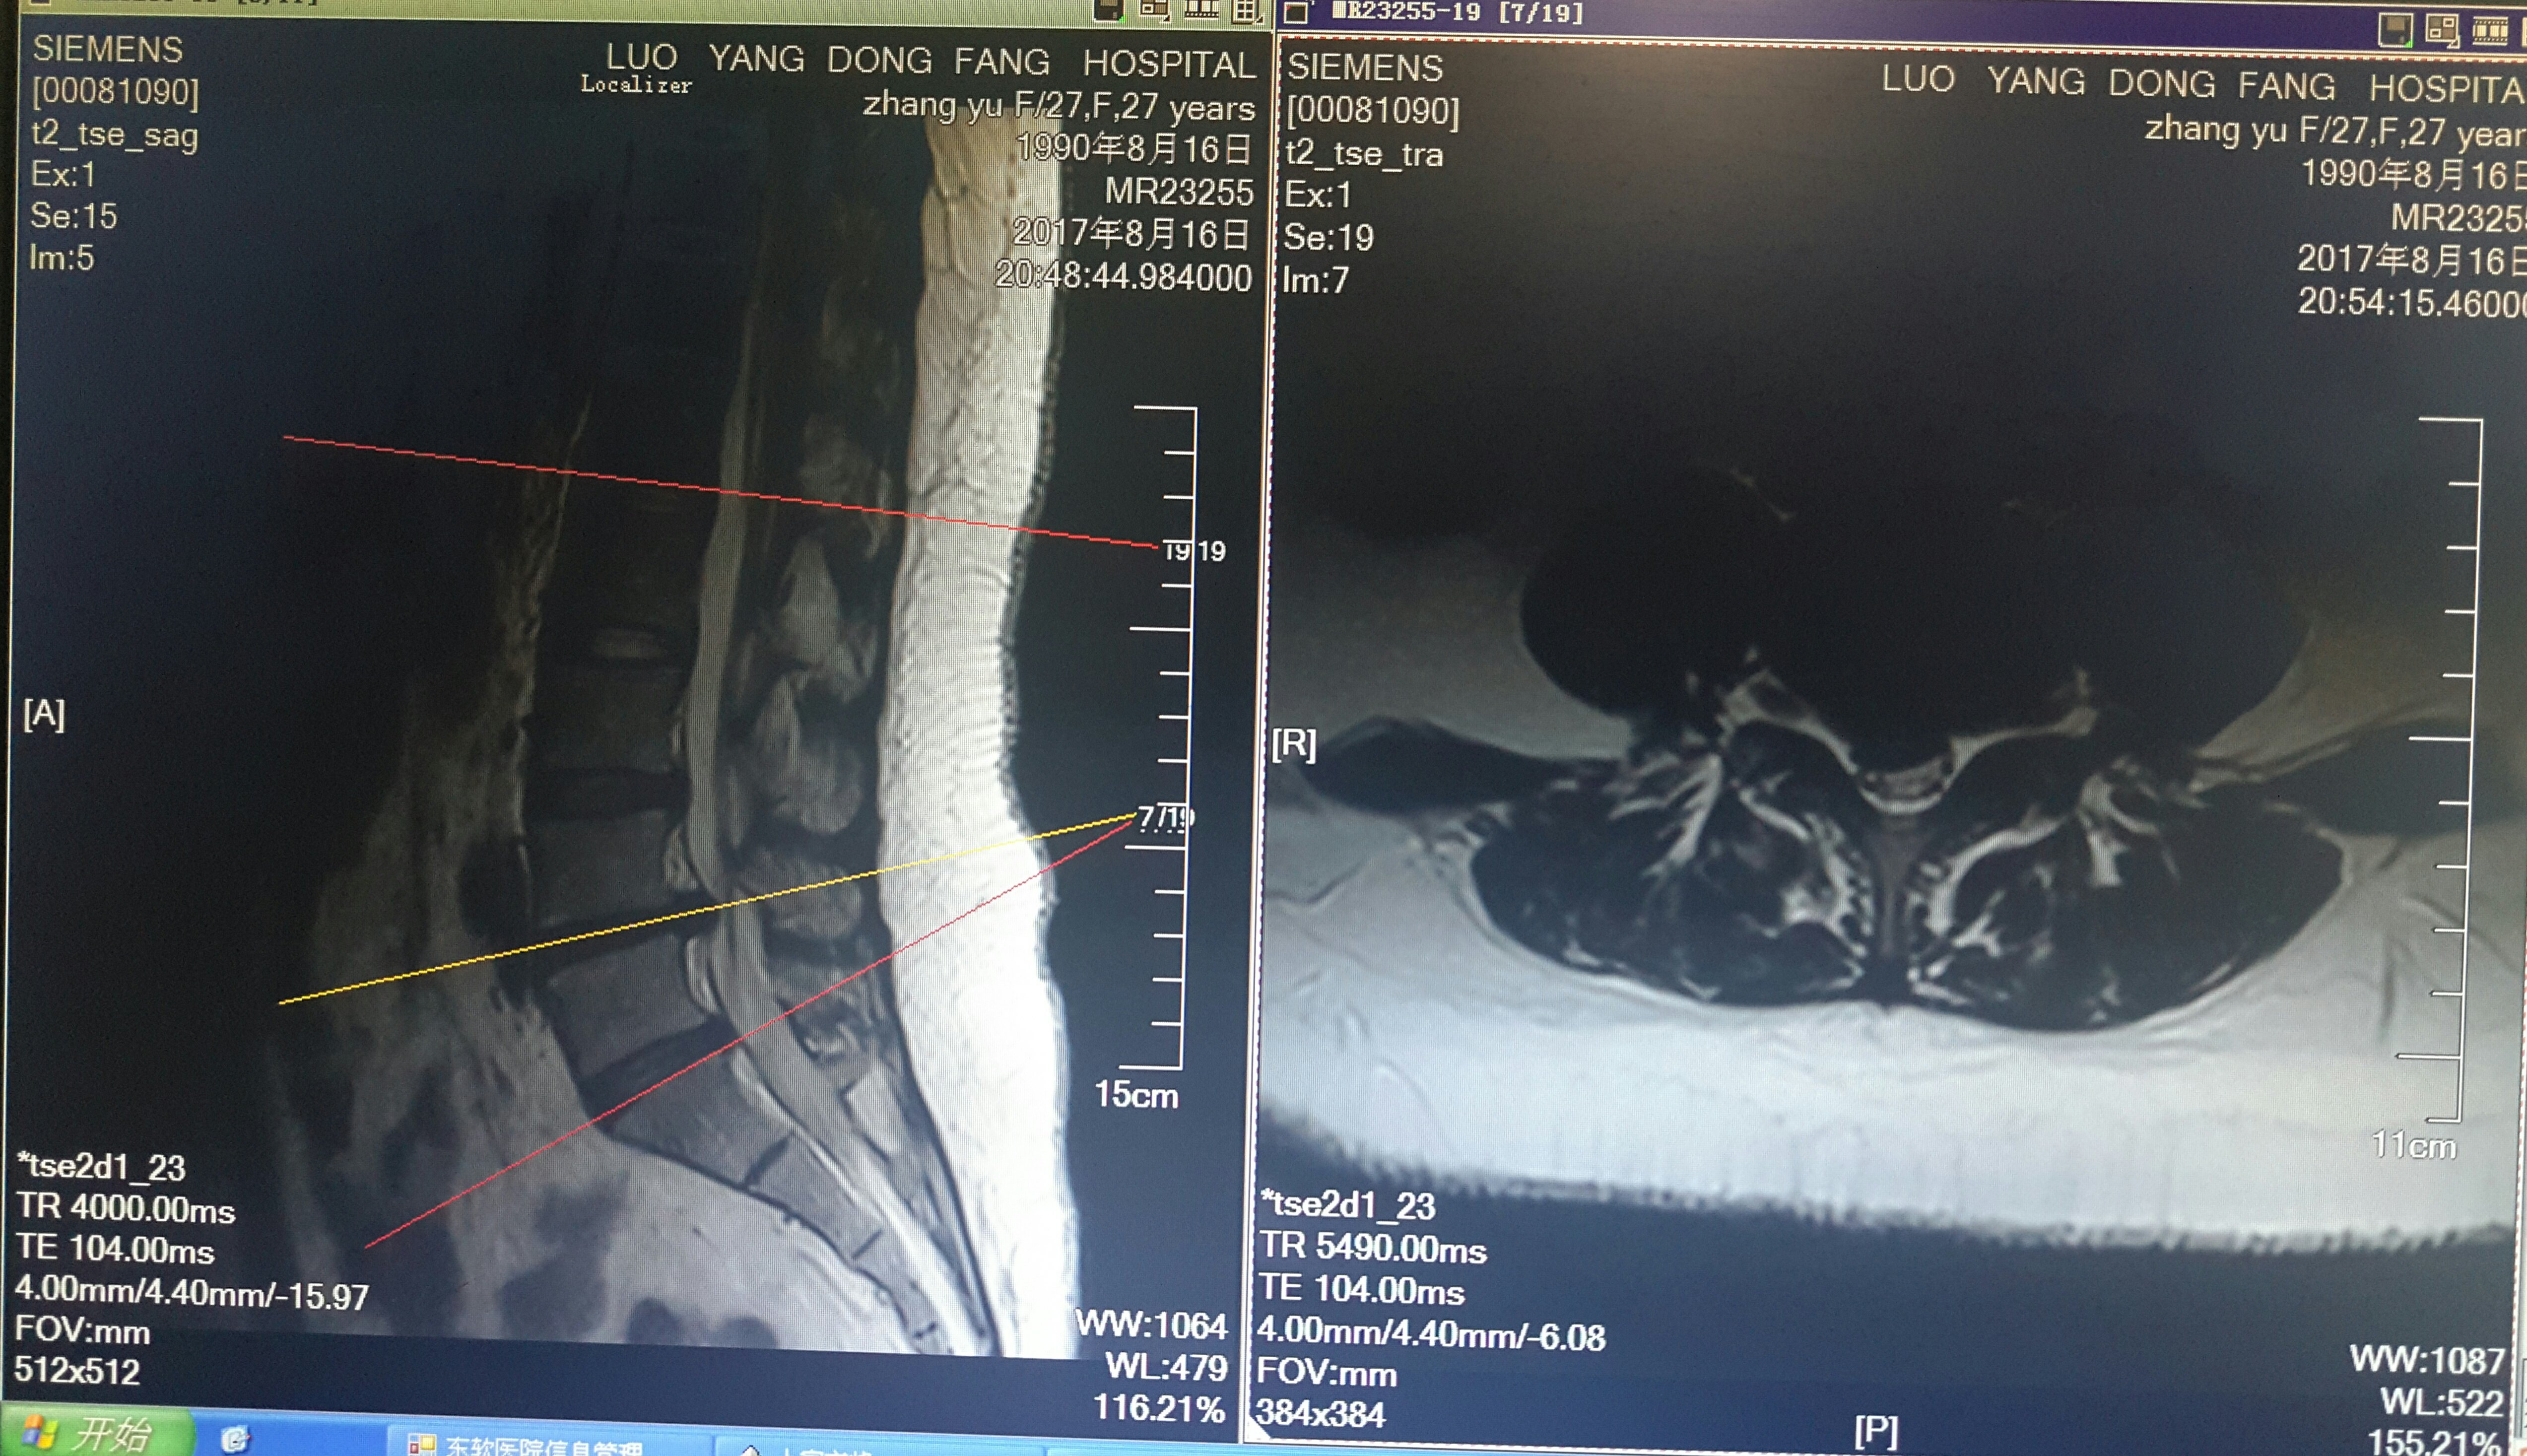

脊柱内镜翻修腰椎间盘突出症胶原酶溶核术后复

5092x2934 - 2124KB - JPEG

脊柱内镜翻修腰椎间盘突出症胶原酶溶核术后复

5194x2450 - 1506KB - JPEG